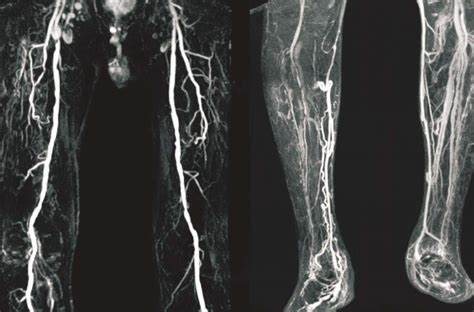

· 影像诊断:床旁超声显示会阴部皮下积气深度达8.2cm,CT血管造影排除睾丸动脉栓塞。